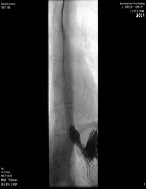

Intrahepatic Bile Duct Cyst Calculus and Gallbladder Stones Treated with Surgery: A Case Report

Koichi Kimura*, Yasuhiro Doi, Yasushi Takii, Ryosuke Tsutsumi, Kensuke Kudou, Norifumi Tsutsumi, Tetsuo Ikeda, Soichiro Maekawa